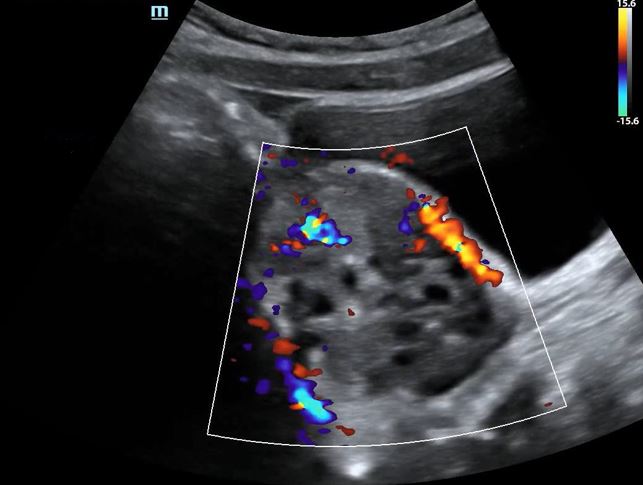

A 17 yo F with no past medical history presents to the ED with acute onset of R sided pelvic pain associated with nausea. A serum hCG is negative. Bedside ultrasound reveals the following. What's the diagnosis? (scroll down for answer)

Answer: Ovarian Torsion

- US is imaging study of choice, however absent Doppler flow is a late finding

- An enlarged ovary alone visualized on US is concerning for diagnosis of torsion, even if dopper flow normal

- Whirlpool sign (shown above) may be seen on US w/ twisting of the vessels